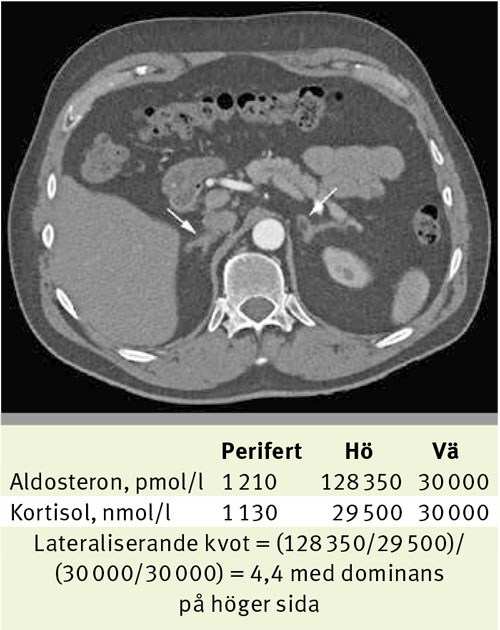

Fallbeskrivning Nödvändig undersökning för många patienter då datortomografi kan leda fel